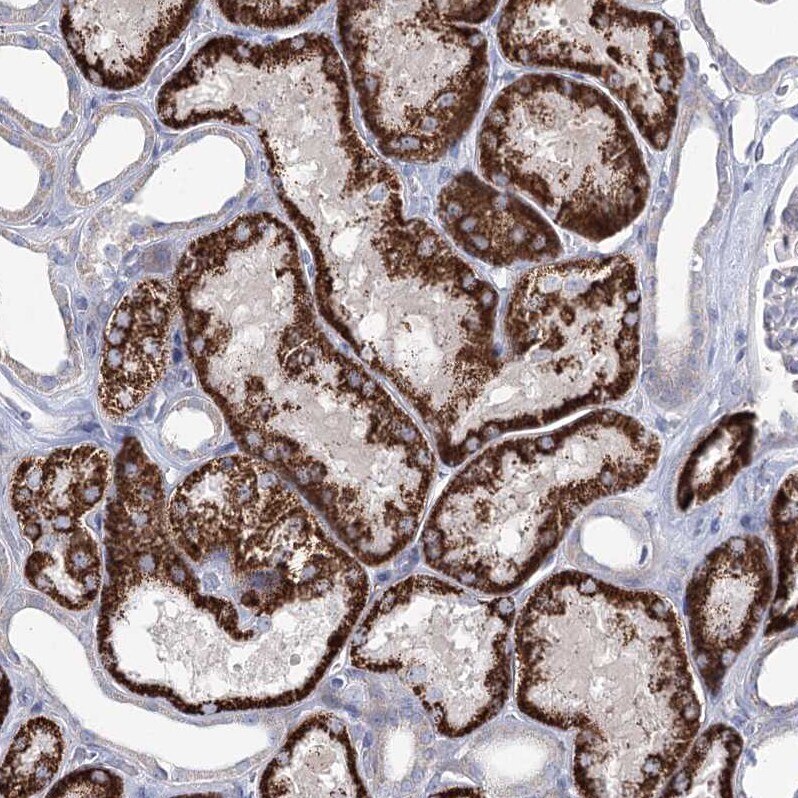

- Immunohistochemical analysis of C5orf42 in human kidney using C5orf42 Polyclonal Antibody (Product # PA5-57810) shows strong granular cytoplasmic positivity in cells in tubules.